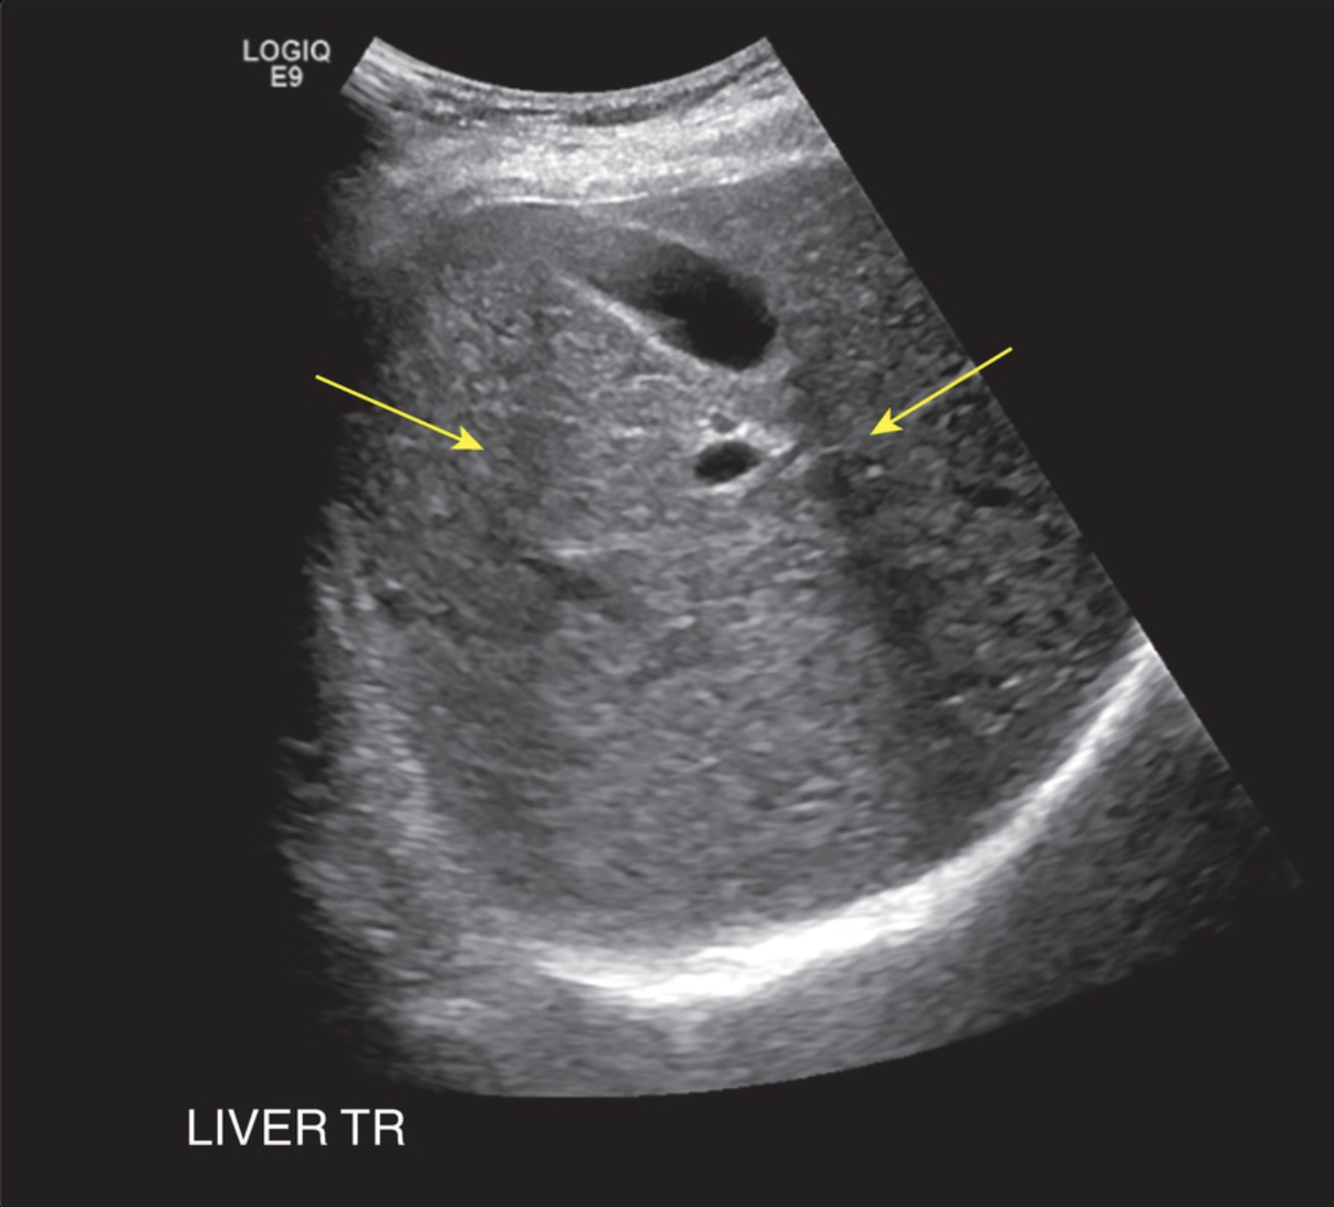

Which phenomenon is responsible for the following US artifact?